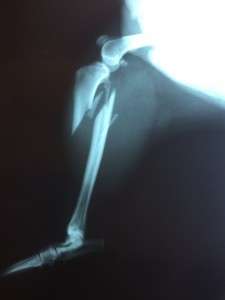

Time passed and she eventually gave birth to her puppies, right there under the abandoned bus where she was living. And most probably another monster with the face of a human took and killed her babies, which she was desperately looking for after. And while looking for her babies a car hit her and broke her legs…

This is how we found her and this is her sad story….We could not possibly have left her there and we took her to the veterinary clinic where she is under investigations right now and they are doing her X-rays and keeping her medicated. For sure the costs for all of this will be high so if you would like to make nay donations, please do so! Any other good thoughts and prayers are helping us a lot!

Update: PAMELA had 3 surgeries, now feels better and we hope to get her home soon, unfortunately we have not managed to cover all veterinary costs.